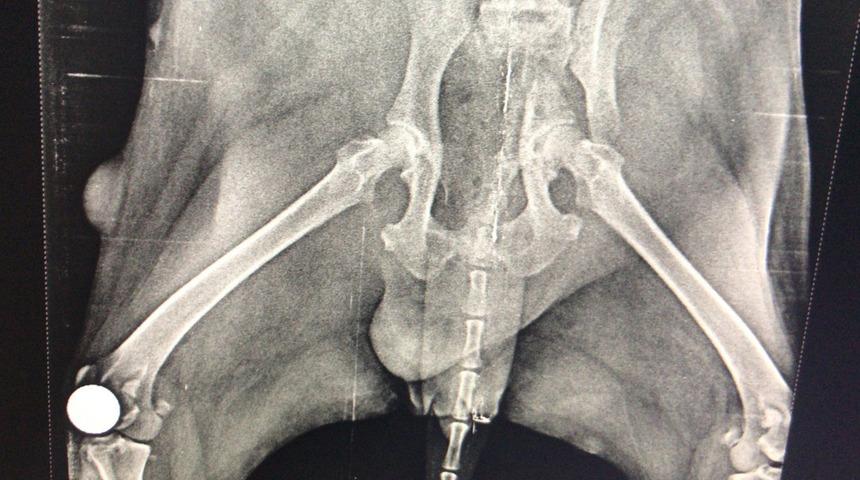

İlçede son dönemlerde çeşitli yaralanmalar ve hastalık sebebiyle veteriner hekime götürülen sokak hayvanlarının çekilen röntgen görüntüleri şoke ediyor. Görüntülerde hayvanların vücutlarında kurşun ve saçmalarla yaşadıkları ortaya çıkıyor.

Bir aracın çarptığı köpek, ağır yaralı olarak veteriner hekime götürüldü. Çekilen röntgende hayvanın vücudunda havalı tüfek saçmaları ile yaşadığı ortaya çıktı.